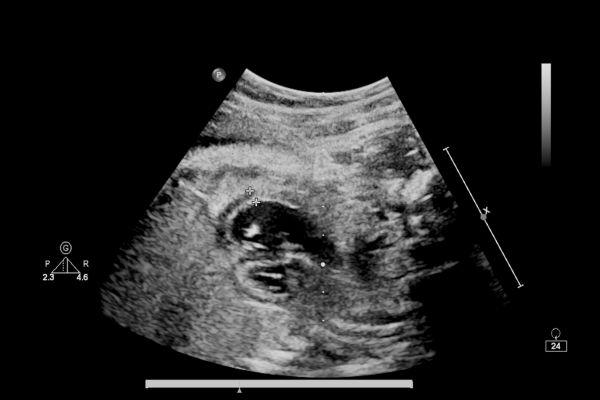

Comprehensive Ultrasound Services

At Heart View Imaging, we deliver high-quality mobile ultrasound services directly to healthcare facilities.

Vascular Studies

Our vascular ultrasound services include carotid duplex (bilateral), lower extremity venous studies for DVT rule-out, limited arterial studies such as ABI or focused lower extremity arterial exams, AAA screening, and renal ultrasound to support timely diagnosis and clinical decision-making.